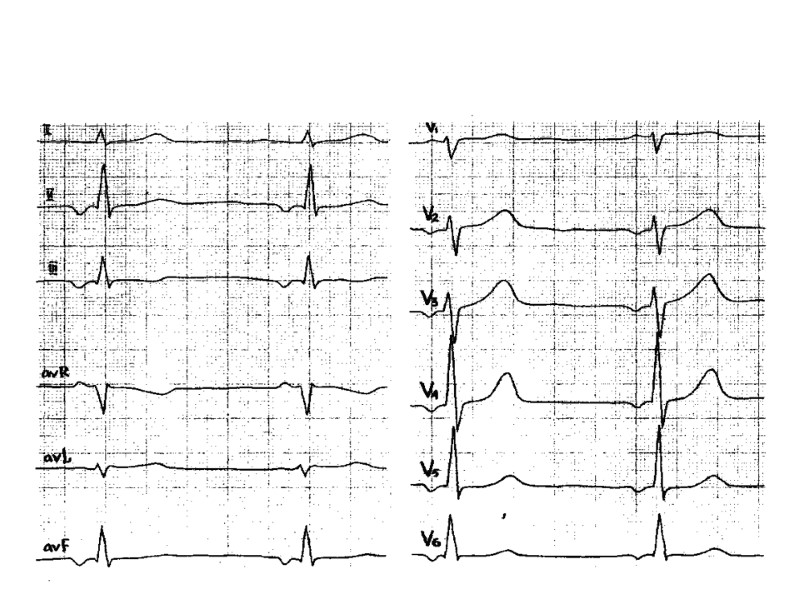

ВЭМ - исходно

ВЭМ- при нагрузке